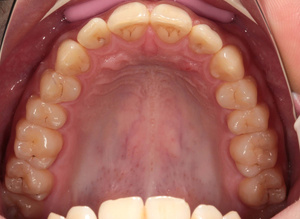

Спасибо всем большое. Дождался заказной вспышки и внутриротовых зеркал с контрастерами.

Все прблемы ушли. Конфигурация техники: Кэнон 550, объектив Кэнон 100/2.8 макро, вспышка Макро

МТ-24ЕХ, зеркала металл YDM.

Ещё. Какие замечания по настройкам?горизонт завален...